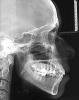

viktoria alekseevna Опубликовано 2 сентября, 2010 Поделиться Опубликовано 2 сентября, 2010 добрый день уважаемые доктора! хочу узнать ваше мнение по поводу моей ситуации. у меня нижняя часть лица достаточно сильно подана вперед что очень портит лицо. но зубы при этом ровные. была у четырех врачей. двое сказали что исправить не получится. одна предложила брекеты без удаления с расширением. другая сказала что без удаления всех четверок выровнять профиль не получится. какое ваше мнение? особенно интересует мнение в варианте с удалением. спасибо за помощ!p.s. на место отсутствующей шестерки буду ставить имплант. Ссылка на комментарий

Премоляр Опубликовано 2 сентября, 2010 Поделиться Опубликовано 2 сентября, 2010 добрый день уважаемые доктора! хочу узнать ваше мнение по поводу моей ситуации. у меня нижняя часть лица достаточно сильно подана вперед что очень портит лицо. но зубы при этом ровные. была у четырех врачей. двое сказали что исправить не получится. одна предложила брекеты без удаления с расширением. другая сказала что без удаления всех четверок выровнять профиль не получится. какое ваше мнение? особенно интересует мнение в варианте с удалением. спасибо за помощ!p.s. на место отсутствующей шестерки буду ставить имплант.Виктория,есть фото зубов в прикусе???По случаю- бимаксиллярная протрузия корректируется именно удалением 4х зубов с целью изменения положения фронт.зубов и ,следовательно, положения губ...тоесть профиль делается немного уплощенным.Но каждый конкр.случай решается индивидуально.Вот по этому и необходимы фото зубов. Ссылка на комментарий

viktoria alekseevna Опубликовано 2 сентября, 2010 Автор Поделиться Опубликовано 2 сентября, 2010 кстати,вполне эстетично и функционально. Насколько всетаки вас беспокоит профиль??? Может лучше оставить все как есть??? Красивая улыбкаспасибо за комплимент улыбке) да, зубы у меня в норме, я знаю, но профиль меня очень беспокоит... на моем худеньком лице очень выпирают челюсти. это !очень! заметно и в профиль и в анфас.а если я выберу вариант с удалением четверок большой ли риск что фронтальные зубы западут назад (тоесть очень поменяют наклон) а не будут сдвигаться вместе с эльвиолярными отростками и визуально будет что челюсти так и останется выпирать, а губы западут. какой прогноз вы можете сделать по снимкам? я готова пожертвовать четырьмя зубами ради профиля, но действительно ли он станет ровнее?? я слишала противоречивые мнения специолистов по этому поводу(... или просто не все хотят браться за такую работу?.. Ссылка на комментарий

Премоляр Опубликовано 3 сентября, 2010 Поделиться Опубликовано 3 сентября, 2010 Да,вы правы...Изменится только наклон зубов в кости...сама кость никуда не денется.Но,изменится и положение губ...я уже писал.Полностью изменить профиль в сторону уплощения возможно только с помощью ортогнатич.хирургии Ссылка на комментарий